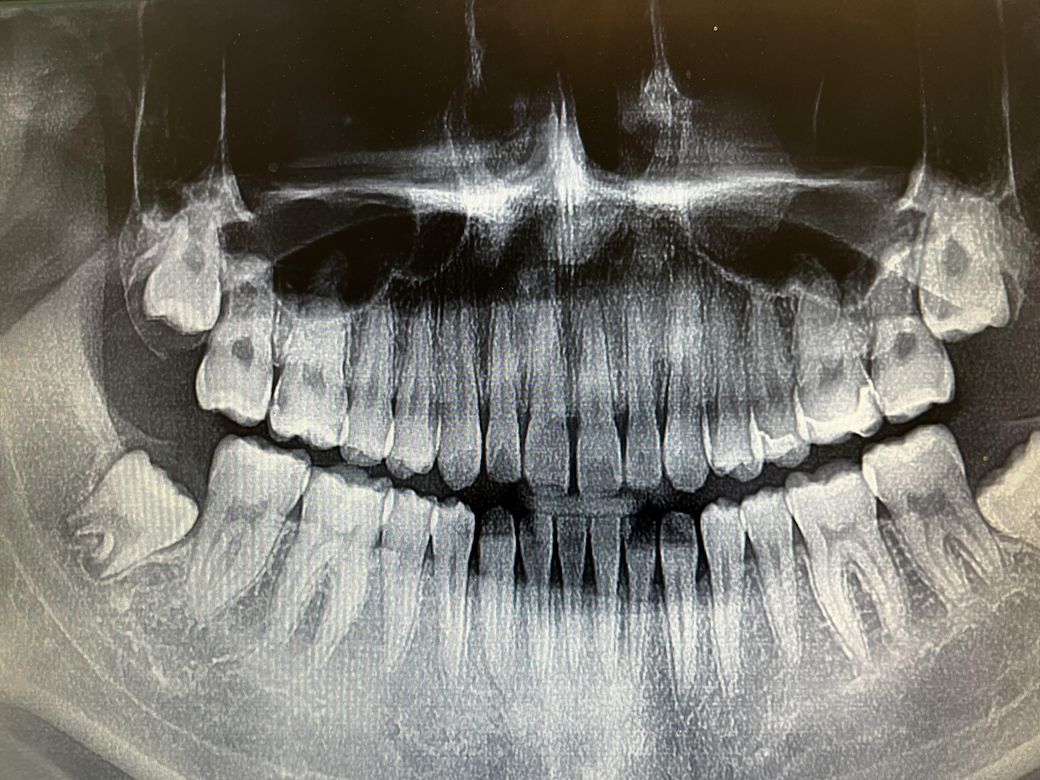

사진속 왼쪽 위에 어금니 치료방법??

사진처럼 왼쪽 위에가 양옆으로 썩었는데 한곳은 인레이로도 가능할수 있다하는데 오늘 간곳은 인레이는 나중에 깨진다고 크라운으로 씌우라하더라구요 신경치료 가능성도 있다늨데 크라운가격이 50만원선이면 싼건지 아니면 인레이가 가능하면 인레이로 하는게 나은지 판단좀 해주세요ㅜ

사진상으로 왼쪽위 어금니는 치아 사이에 충치가 많이 진행된 상태 같습니다. 신경치료를 하셔야될것같습니다.

일반적으로 인접면에 충치가 생기면 보철 치료를 하는 경우가 많이 있습니다. 크라운이나 인레이 치료를 하게 됩니다. 사진으로만 봤을 경우에는 신경 치료에 필요가 없을 것으로 보이나 충치를 제거하고 쉬는 증상이 심하다면 신경치료를 하는 것이 좋을 수 있습니다. 자세한 확인을 위해서 치과에서 진료를 받아보는 것을 권유드립니다.

양쪽옆으로 썩어 인레이를 한다면 양쪽으로 긴 인레이를 한다는 뜻인데 mod인레이라고 합니다 mod인레이는 크랙 유발될 확률이 너무 높아 잘 안합니다 크라운이 더 나은 선택입니다

크라운 50이면 비싼거 아닙니다